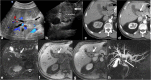

Malignancies of the biliary tract include cholangiocarcinoma, gallbladder cancers and carcinoma of the ampulla of Vater. Biliary tract adenocarcinomas are the second most common primary hepatobiliary cancer. Due to their slow growing nature, non-specific and late symptomatology, these malignancies are often diagnosed in advanced stages with poor prognosis. Apart from incidental discovery of gall bladder carcinoma upon cholecystectomy, early stage biliary tract cancers are now detected with computed tomography (CT) and magnetic resonance imaging (MRI) with magnetic resonance cholangiopancreatography (MRCP). Accurate characterization and staging of these indolent cancers will determine outcome as majority of the patients' are inoperable at the time of presentation. Ultrasound is useful for initial evaluation of the biliary tract and gallbladder masses and in determining the next suitable modality for further evaluation. Multimodality imaging plays an integral role in the management of the biliary tract malignancies. The imaging techniques most useful are MRI with MRCP, endoscopic retrograde cholangiopancreatography (ERCP), endoscopic ultrasound (EUS) and positron emission tomography (PET). In this review we will discuss epidemiology and the role of imaging in detection, characterization and management of the biliary tract malignancies under the three broad categories of cholangiocarcinomas (intra- and extrahepatic), gallbladder cancers and ampullary carcinomas.